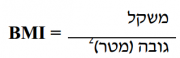

| 19:09, 18 באוגוסט 2014 | Bmi1.png (קובץ) |  |

6 קילו־בייטים | Motyk | 1 | |